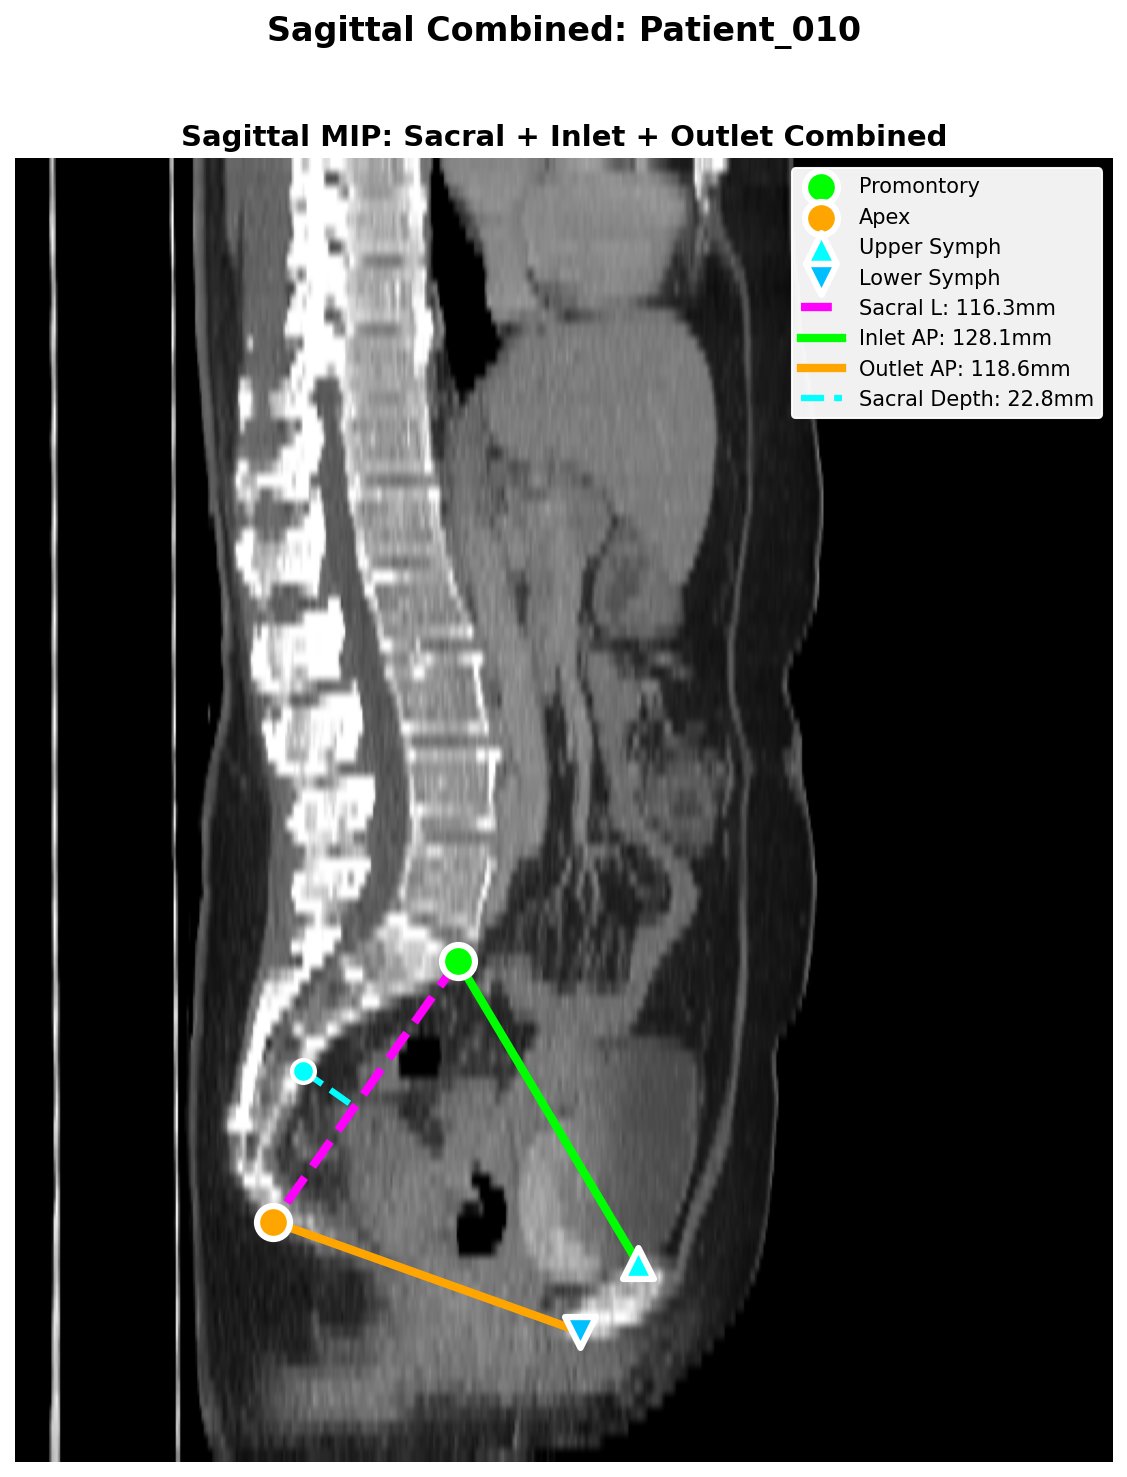

QC Output Example

Sagittal QC figure showing automated landmark detection and pelvimetric measurements: sacral length (magenta), inlet AP (green), outlet AP (orange), and sacral depth (cyan).

| Inlet AP (mm) | Promontory → Upper Symphysis | | Outlet AP (mm) | Coccygeal Apex → Lower Symphysis | | Outlet Transverse (mm) | Intertuberous diameter | | Outlet Area (cm²) | Ellipse approx: π/4 × AP × Transverse | | Sacral Length (mm) | Promontory → Coccygeal Apex | | Sacral Depth (mm) | Max anterior concavity |